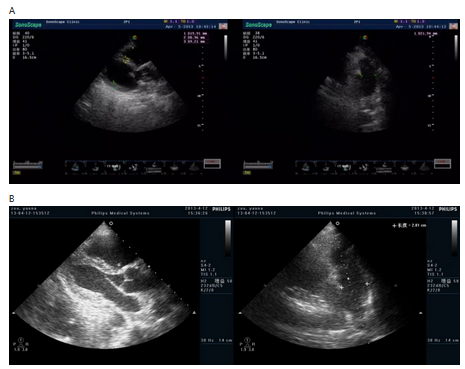

从B超的动态演变可见(图30-2、表3):

1.肺动脉压在溶栓后逐步下降,溶栓后2小时下降幅度最明显,下降25%,约10天后恢复正常;

2.左室舒张末期内径(LVDd)因肺动脉压升高、右室压力增高,泵血减少使左室前负荷减少,同时因右室压力进行性增高使室间隔舒张期反向运动,室间隔左移明显,使左室内径进一步减小,经溶栓后LVDd 2小时扩大13%,24小时后扩大25%,LVDd的扩大幅度轻度滞后于肺动脉的下降,但与肺动脉压的下降幅度平行;

3.溶栓后右房的改善在数小时内明显;

4.溶栓后右室内径的缩小在最初几天内不明显,明显滞后后左室的扩张幅度,左房的改变在溶栓后也明显改善。

5.每搏输出量在溶栓后逐步增加的,而左心射血分数逐步下降,考虑为患者在心肌缺血受损后,虽然左心舒张末期容积增加,但左心收缩能力尚未恢复所致。Goldhaber等[16]观察对发病时合并急性右心功能不会患者,t-PA溶栓后24 h内心脏超声检查提示右室收缩期室壁运动和左室舒张未面积有显著改善,三尖瓣反流和肺动脉压均明显降低。Metz等[17]观察到溶栓后48小时后右室扩张、肺动脉高压、三尖瓣反流、左室射血分数改善明显。本病例B超的动态演变提示在溶栓后肺动脉压和左室在数小时内的改善可能更明显。

图30-2 B超动态表现

A.入院时 B.溶栓前 C.溶栓后1天 D.溶栓后5天